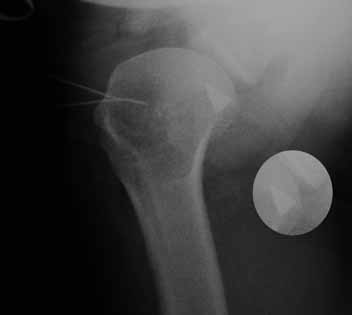

Больная В. 41 год. Во время выполнения операции Розенштейна – пересечение сухожилия двуглавой мышцы плеча

(транспозиции сухожилия двуглавой мышцы плеча, с проведением ёё под ротаторами плеча, к клювовидному отростку) произошел перелом конца съёмного лезвия скальпеля (Фирма: TRO-Microcut. №21; Lot 21/889-01 Exp: 2013-02).

Снимок сделан во время операции в положении бльного на спине - аксиальная проекция. Игольчате метки - передняя поверхность плечевого сустава в этом мете осуществлен доступ. Прямая проекция обрезана. Фрагмент рапологается по центру головки на самом краю снимка.